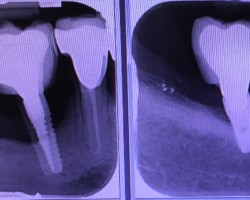

Connexion interne ou externe

Là encore, aucune étude n’a pu montrer de relations directes entre le type de connexion et le développement d’une péri-implantite cependant, les études ont montré une meilleure stabilité des connections internes et notamment des connexions pseudo cône morse limitant la perméabilité du micro-joint et donc le risque de développer une contamination au niveau du site osseux.

Bone level or Tissue level

S’il est vrai, que pour des raisons de contamination bactérienne, notamment au niveau des micro joints des implants, il est conseillé de mettre ce micro-joint à l’extérieur du niveau osseux, et que le fait d’avoir un col lisse qui place ce micro-joint au-dessus des tissus, l’adhésion des tissus à la surface titane de l’implant est très bonne.

Cependant, on aperçoit également des péri-implantites sur des tissues levels…

On privilégiera donc un implant avec une connexion interne pseudo cône morse, plutôt rugueux (modéré) pour améliorer l’ostéointégration et avec un col lisse plus ou moins important pour la stabilité des tissus et positionner le micro-joint en dehors de l’os.